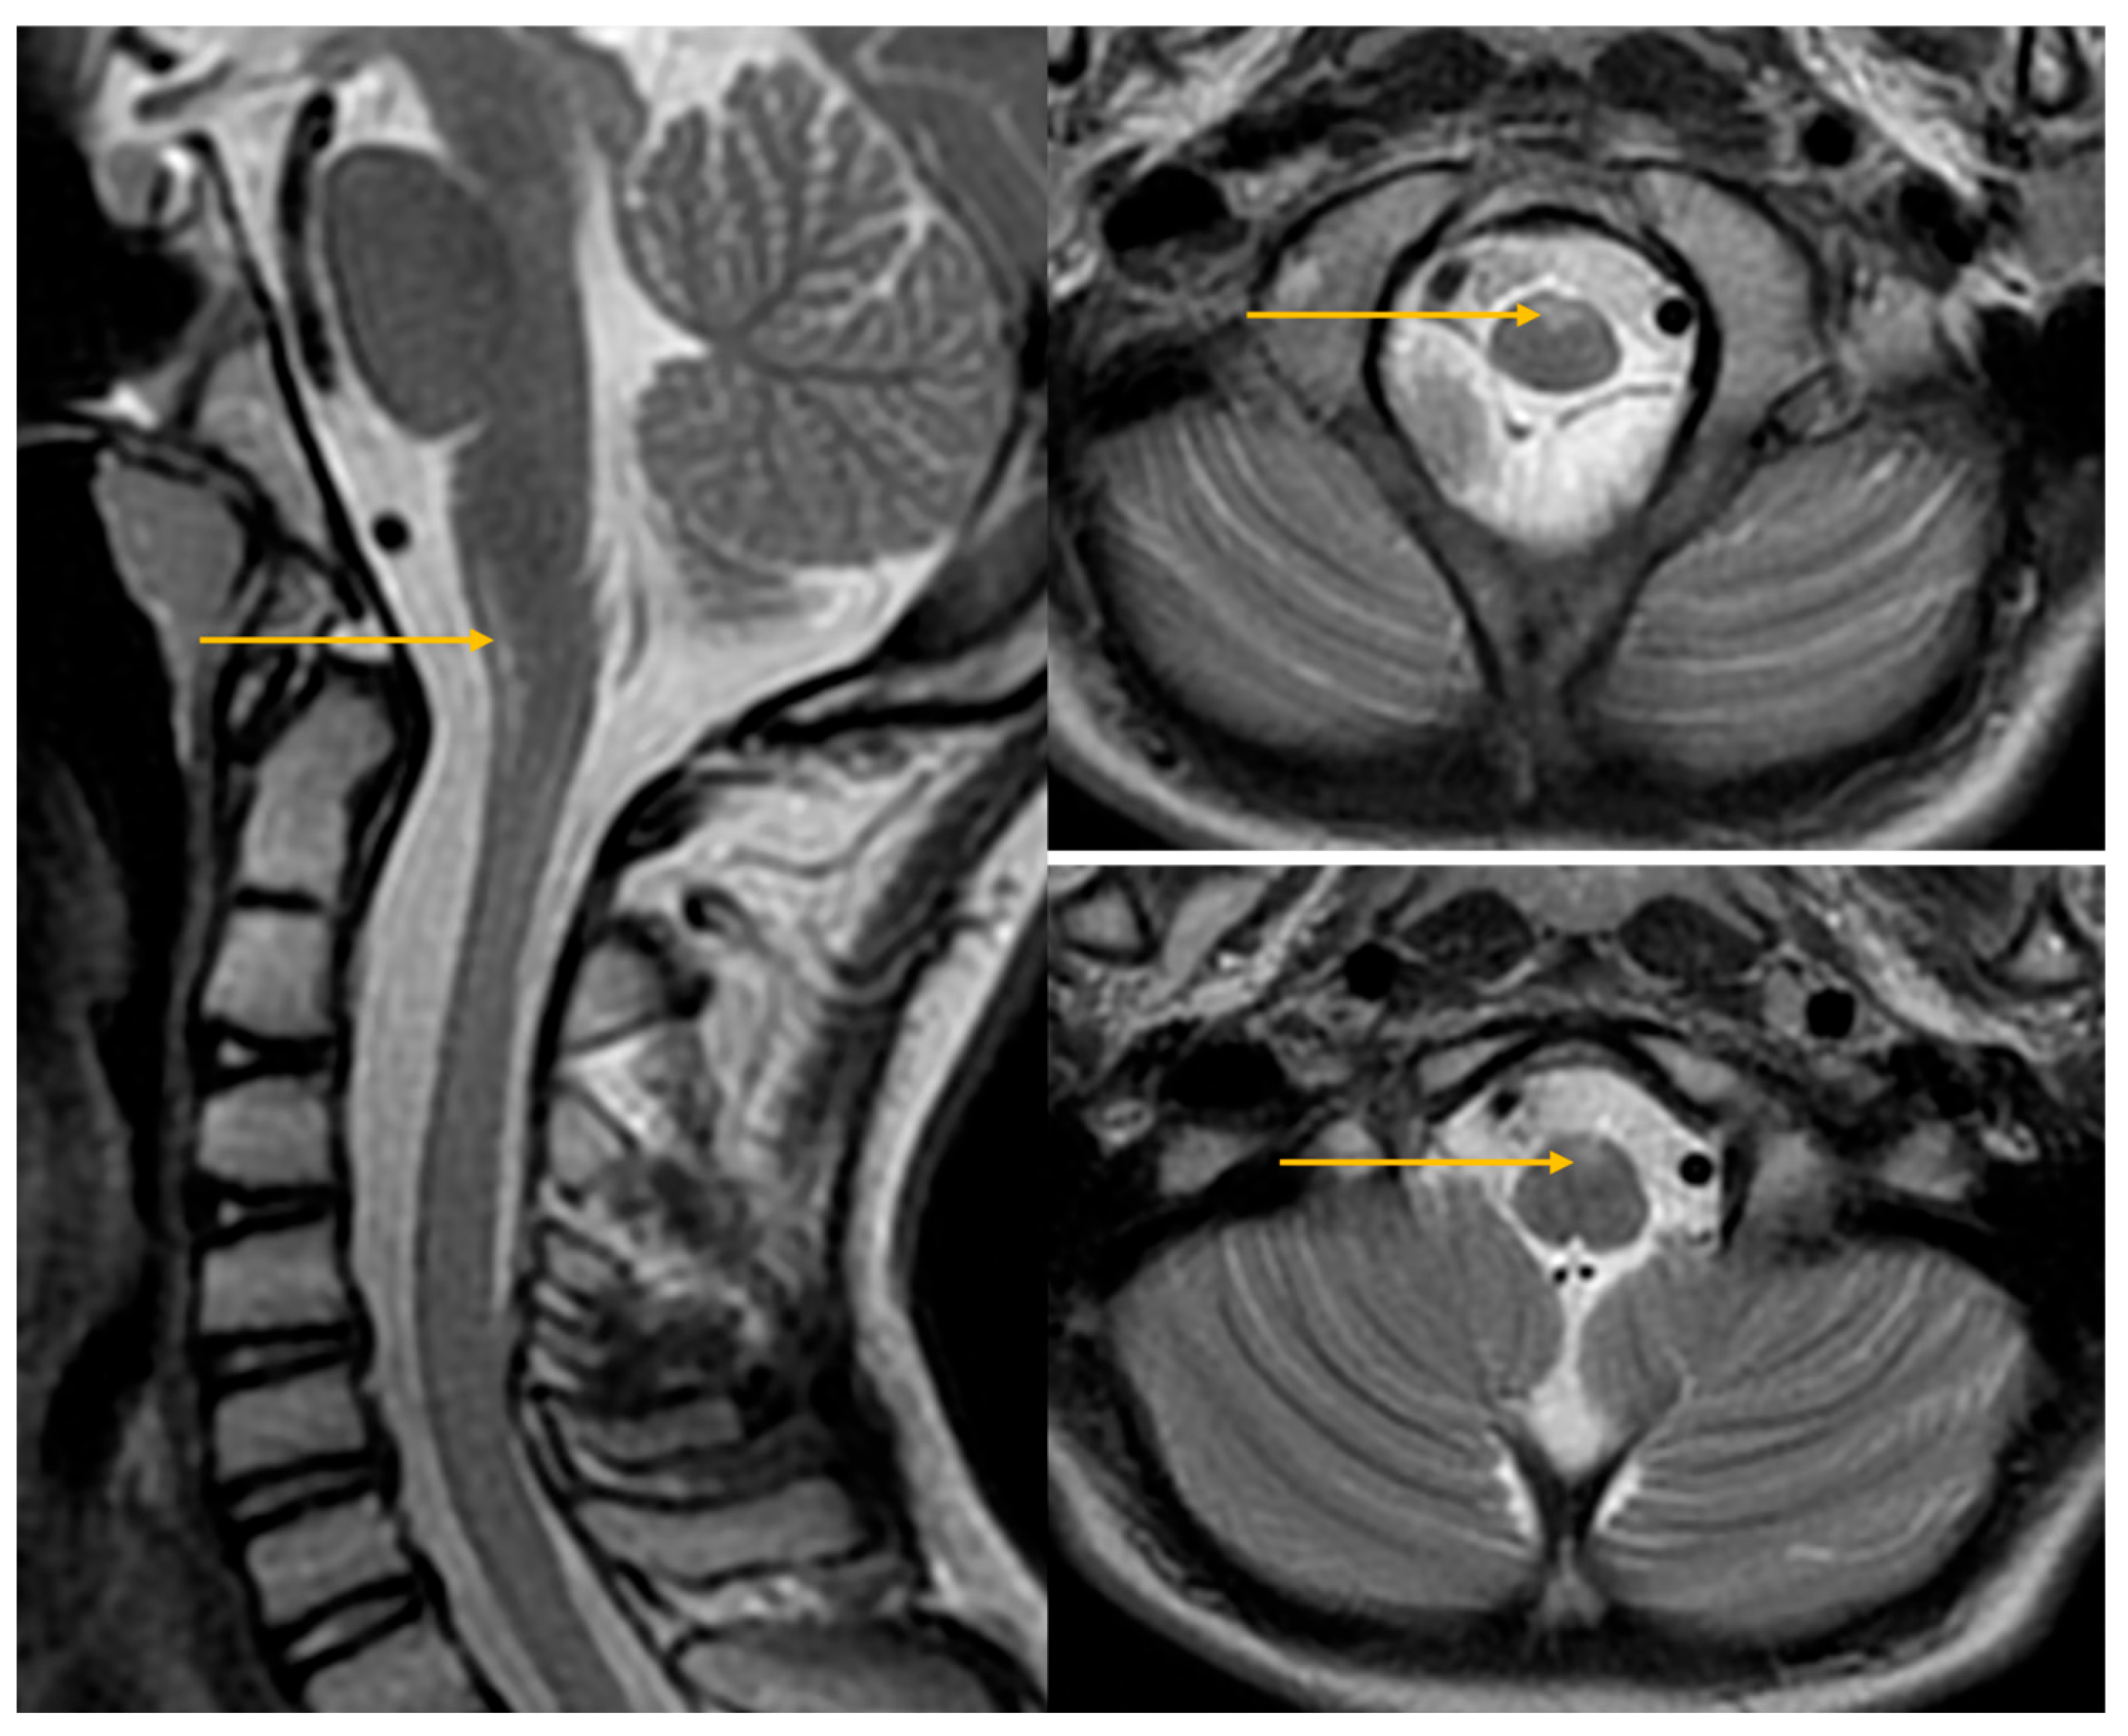

| Abnormal signal intensity of the anterior portion of the medulla oblongata | Yes | NA | Yes | Yes | Yes | Yes | Yes |

| Atrophy of the medulla | No | NA | No | Yes | Yes | Yes | Yes |

| Atrophy of the cervical spinal cord | Yes | NA | No | Yes | Yes | Yes | Yes |

| Signal abnormalities in the cerebellar white matter or hilus of the dentate nucleus | No | NA | No | No | No | No | No |

| Cyst formation in white matter around the anterior horn of the lateral ventricles | No | NA | No | No | No | No | No |

| Ventricular garlands | No | NA | NA | NA | NA | NA | NA |